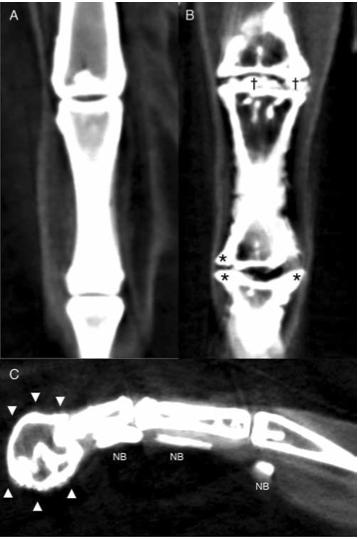

Figure 3. Reconstructed dorsal plane CT image of a normal MTP and IP joint (A), reconstructed dorsal plane CT image of a severely affected MTPjoint and IP joint (B) with periarticular new bone formation (as- terisks *) and new bone formation within the joint space (daggers â ), and reconstructed sagittal plane CT image of a severely affected digit (C) with a misshaped distal phalanx surrounded by a rim of new bone (arrowheads â²) and linear mineralization plantar to the digit within the extensor tendons (NB).